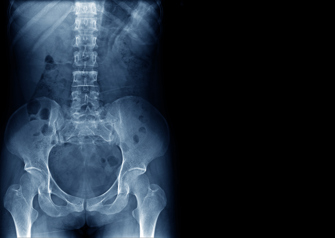

Dr. Frank Phillips, a minimally invasive spine surgeon at Midwest Orthopaedics at Rush and Director of the Division of Spine Surgery at Rush University Medical Center, recently traveled to Nagoya, Japan to speak at the second SOLAS Japan Annual Meeting. Dr. Phillips, who presented “Fifteen years of lateral access surgery: Lessons learned and future horizons,” served as the meeting’s keynote speaker. He is a past president of SOLAS.